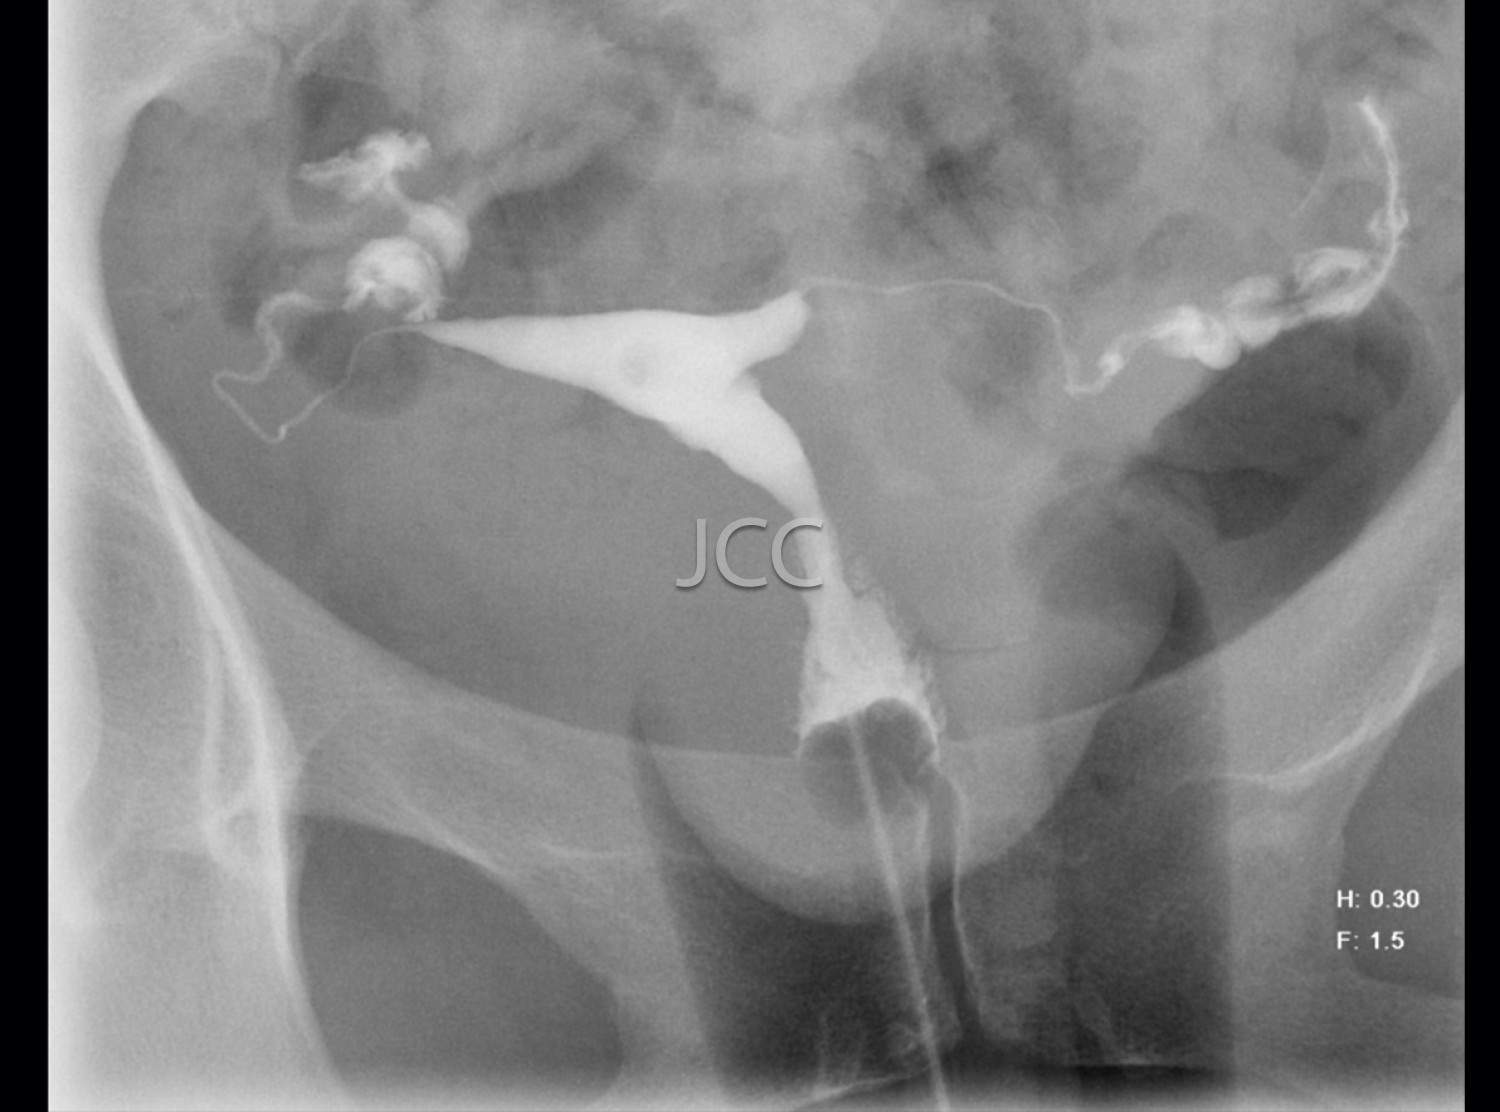

Digital Acquisition X-Ray - Hysterosalpingography

• The patient should take Clamoxyl 1g (amoxicillin) (capsules) once every 8 hours starting on the day of the examination and prolong the treatment for 5 days.

• The examination should be performed on the last day of the menstrual period, up to a maximum of 2 days after.

• In case of allergy to penicillin, Clamoxil should be replaced by E.S.E - 1000ml.